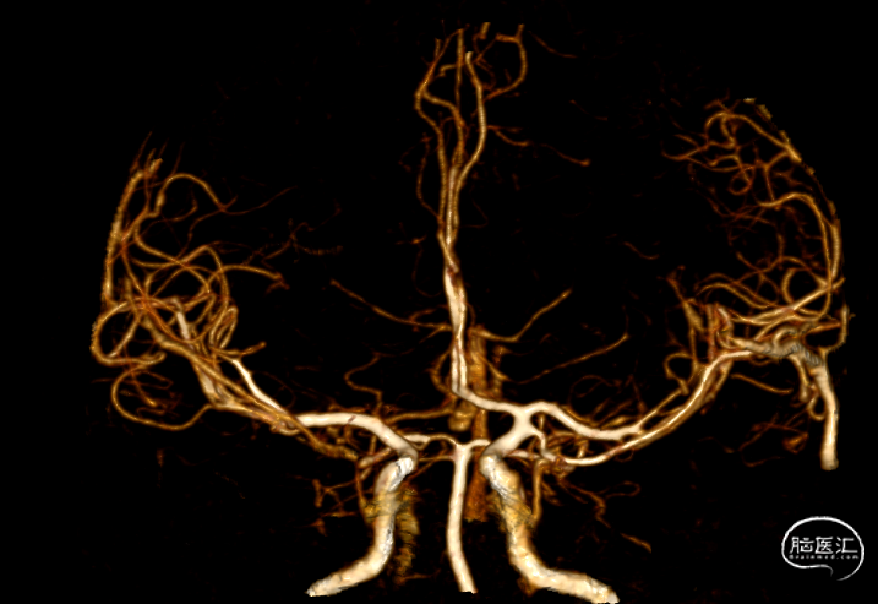

头颈CTA:右侧颈内动脉闭塞,请结合临床。

入院头颅CTA:右颈内闭塞。

右侧颈内动脉闭塞:

MCA的解剖变异类型包括副MCA、重复MCA、重复MCA起源变异、MCA开窗畸形、MCA网状变异(树枝样MCA)等异常。

本文病例经DSA证实为MCA由颈内动脉末端发出,为DMCA,且为主干的大脑中。

重复大脑中动脉(DMCA):起源于颈内动脉的血管,与大脑中伴行。发生率约为0.2-2.9%。

副大脑中动脉( AMCA):是指起源于大脑前动脉,行经侧裂并与大脑中动脉(MCA)伴行,参与MCA供血区供血的脑血管变异,文献报道发生率约为0.3-4%。

A:分叉过早;B:开窗;C:AMCA;D:DMCA;E:正常